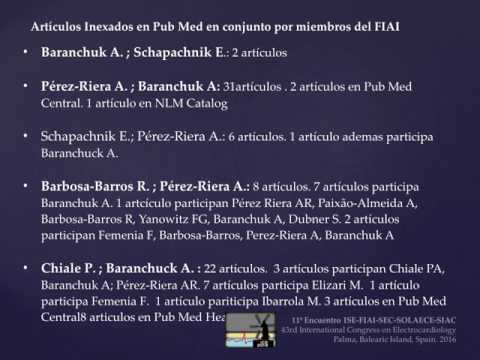

Enfermedad de Chagas 2017: después del BENEFIT. Parte 6/6

Enfermedad de Chagas 2017: después del BENEFIT. Parte 5/6

Enfermedad de Chagas 2017: después del BENEFIT. Parte 4/6

Enfermedad de Chagas 2017: después del BENEFIT. Parte 3/6

Enfermedad de Chagas 2017: después del BENEFIT. Parte 2/6

Enfermedad de Chagas 2017: después del BENEFIT. Parte 1/6